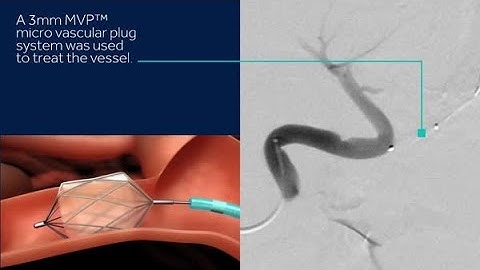

MVP™ Micro Vascular Plug System. Rethink embolization. With one device.